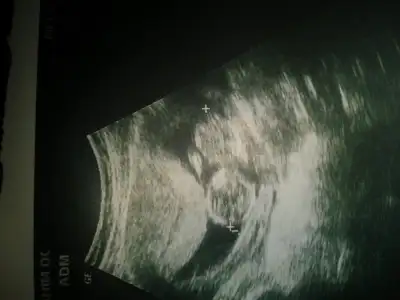

dr soylemeden siz gorun genital nub teorisi ( bebegin cinsiyeti)

cnm burası sırtı bak omur kemiklerine maşallah:)

gözükmüyor mu nub u :) ilk bebek olduğu için ben anlamıyorum da pek

Foton yokmu canimbenim bebeğim için doktor büyük ihtimalle erkek dedi. ama ben hala emin olmadigi için bir de siz yorumlayin istedim mümkün mu acaba

https://imageshack.us/a/img901/5918/RHqYfh.jpg sonunda yuklendi kizlar yorumlarinizi bekliyorum

kaç haftalıkhttps://imageshack.us/a/img901/5918/RHqYfh.jpg sonunda yuklendi kizlar yorumlarinizi bekliyorum

burda 13+4kaç haftalık

https://imageshack.us/a/img901/5918/RHqYfh.jpg sonunda yuklendi kizlar yorumlarinizi bekliyorum

doktor erkege benziyo dedi ama bende bu nub olayini pek cozemedigim icinAaa bu prensessss

Abla gozumun onunde nedense erkek diye hayal ettim cepten baktigim icin nubu pek goremedim ama erkek buEki Görüntüle 1325074 Benim kuzumada bakiverin yaa

erkek buEki Görüntüle 1325074 Benim kuzumada bakiverin yaa

üsteki resimde erkek gibi geldi ama alttaki resimdede bi şey göremedim vallaburda 13+4